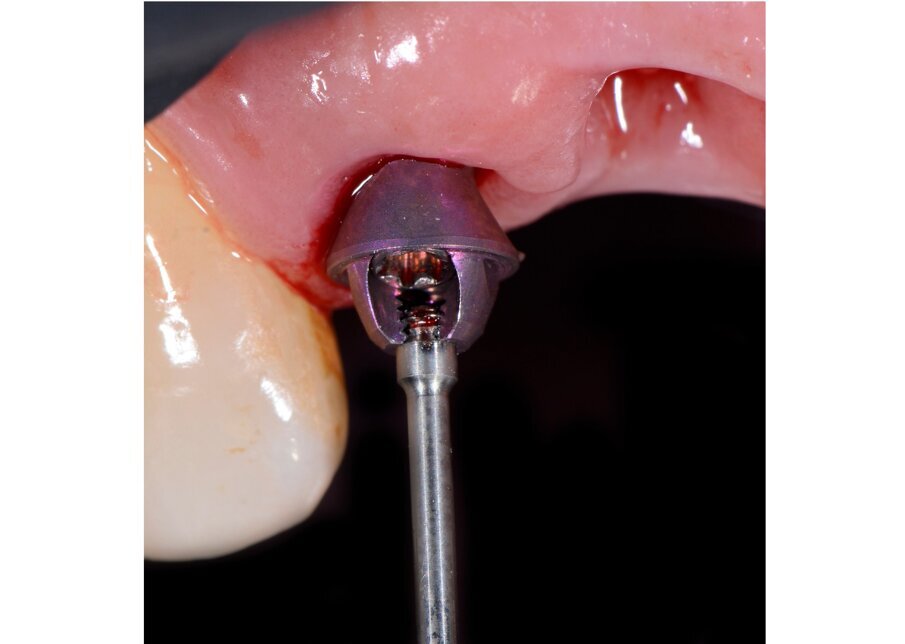

Il nostro obiettivo è quello di riuscire a dare alla paziente un provvisorio immediato nell’arco di due ore. Questo diventa possibile perché abbiamo utilizzato un flusso digitale fin dall’inizio. In laboratorio vengono realizzate la dima chirurgica (Figg. 16, 17), la dima protesica (Fig. 18) e anche il provvisorio (Figg. 19-21) che contiene delle alette di riposizionamento. Il tutto gestito con modelli digitali sui quali saremo in grado di funzionalizzare il provvisorio post-chirurgico (tecnica DIL). In un caso come questo se utilizziamo un flusso digitale possiamo evitare subito dopo la chirurgia di rilevare un’impronta degli impianti inseriti. Infatti, utilizziamo una dima chirurgica che ci faciliterà le fasi di intervento. La dima ci consentirà di non fare lembi e nessuna incisione di rilascio (Fig. 22), dopo aver inserito gli impianti (BLX Straumann) (Figg. 23-31) e aver controllato il loro alloggiamento, inseriamo sugli stessi dei transfert da impronta (Fig. 32).

Fig. 23- Posizionamento della dima.

Fig. 24 - Visione Occlusale.

Fig. 25 - Preparazione letto implantare.

Fig. 26 - Impianto BLX Straumann.

Fig. 27 - Posizionamento impianto 1.2.

Fig. 28 - Alloggiamento finale.

Fig. 32 - Transfert avvitati sugli impianti.

Alloggiamo la dima protesica (Fig. 33), e blocchiamo i transfert con della resina trasparente (tecnica DIL) (Figg. 34, 35). In questo modo possiamo far riposare il paziente in studio dopo appena 35 minuti dall’inizio dell’intervento. La dima protesica, infatti (Fig. 36) con i transfert inseriti viene completata con l’unione degli analoghi ai transfert (Fig. 37). L’insieme così composto viene riadattato sul modello master digitale iniziale (Figg. 38-40) sul quale era stata costruita sia la dima chirurgica che la dima protesica come anche il provvisorio. Gli analoghi vengono bloccati sul modello con resina trasparente (Figg. 41-43). Alloggiamo il provvisorio sul modello master digitale così ottenuto (Figg. 44, 45).